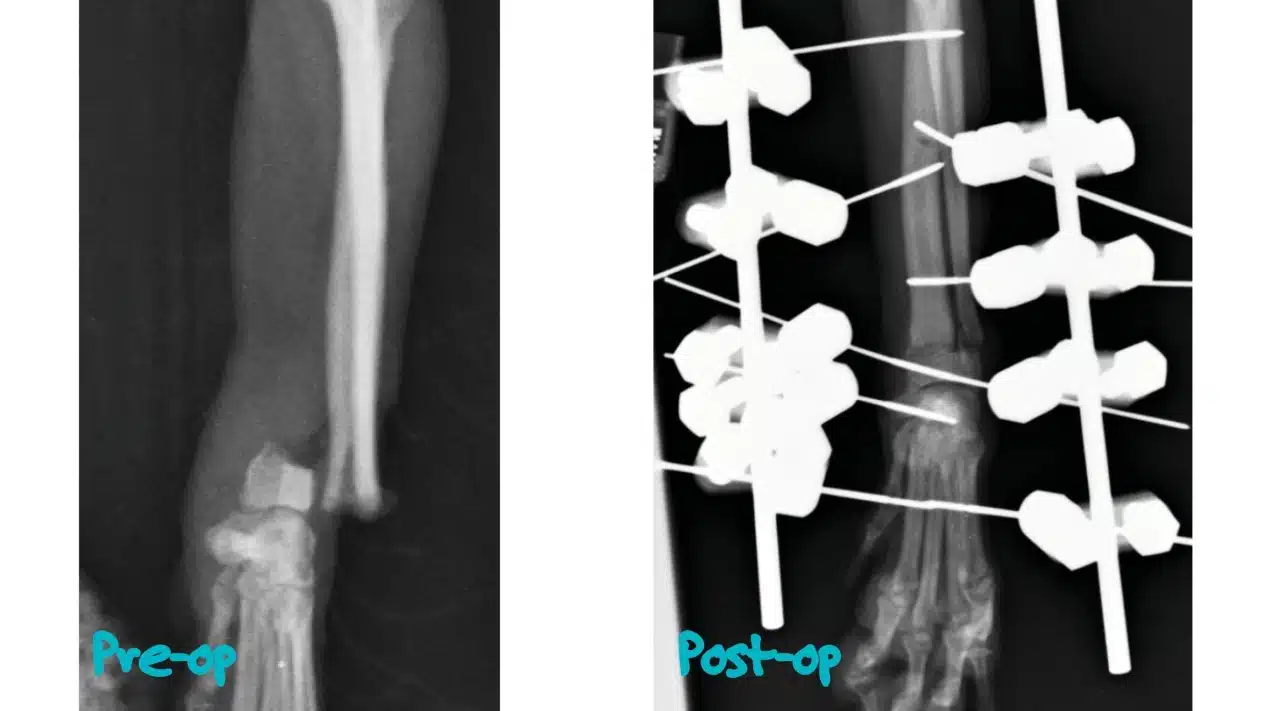

En la clínica veterinaria, el médico diagnosticará la lesión mediante radiografías digitales y ecógrafos. El veterinario determinará la complejidad de la lesión y elegirá el mejor método de tratamiento individualizado para tu cola de caballo, de modo que tu mascota pueda volver a una vida normal lo antes posible. El diagnóstico es necesario para determinar el método de tratamiento más eficaz para la fractura: puede consistir en fijar la extremidad del animal, dejarla en reposo, restringir la actividad física, tomar medicación o, posiblemente, cirugía, fisioterapia y un periodo especial de rehabilitación.

Una fractura de pata puede ser completa o incompleta, cerrada o abierta, única o múltiple. Para tratar las fracturas complejas, la medicina veterinaria moderna utiliza el método de la osteosíntesis, una operación quirúrgica para fijar el hueso dañado con construcciones especiales: placas, rayos, clavos, tornillos. Inmediatamente después de dicha operación, el animal empieza a ponerse de pie sobre la pata. El método conservador -el enyesado- sólo puede aplicarse cuando la cirugía no es posible. En el 90% de los casos, una pata fracturada en perros y gatos se cura muy rápidamente si se prestan los primeros auxilios a tiempo y se elige correctamente el método de tratamiento.